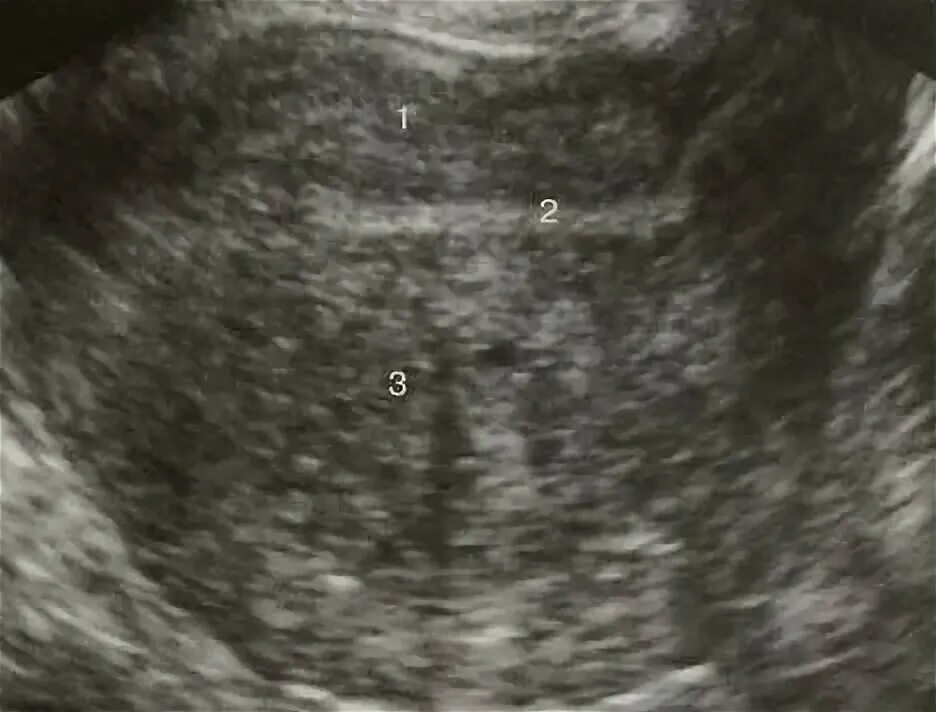

Диффузные изменения миометрия аденомиоз